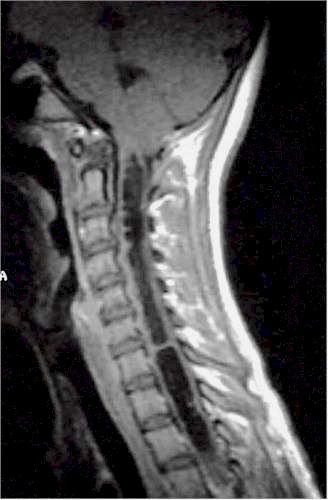

| Siringomielia

cervico-dorsale RM. |

Esito

postchirurgico. |

Due

anni dopo. |